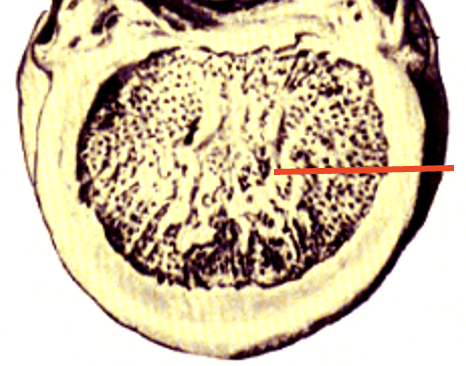

butterfly

center of the spinal cord; contains neurons and glia (grey matter)

grey matter

primarily made up of neurons (cell bodies)

white matter

primarily made up of myelinated axons

dorsal column/funiculus

white matter located in between dorsal horns; contain multiple tracts

sensory information (ascending)

contains large diameter processes of dorsal root ganglia

ventral column/funiculus

white matter located between two ventral horns; contain multiple tracts

motor informsation (descending)

lateral funiculus

between lateral edge of dorsal and ventral horns; contains multple tracts

sensory and motor tracts

ascending and descending tracts

anterior white commissure

located dorsal to the anterior median fissure

contains axons from one side of spinal cord to another